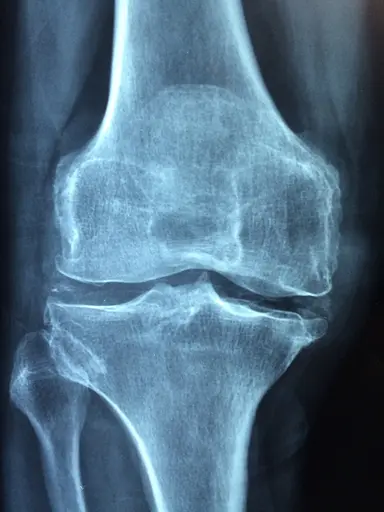

Q3.What is this type of image called?

Q5.This person has had an accident. Look at the X-ray, what can you see?